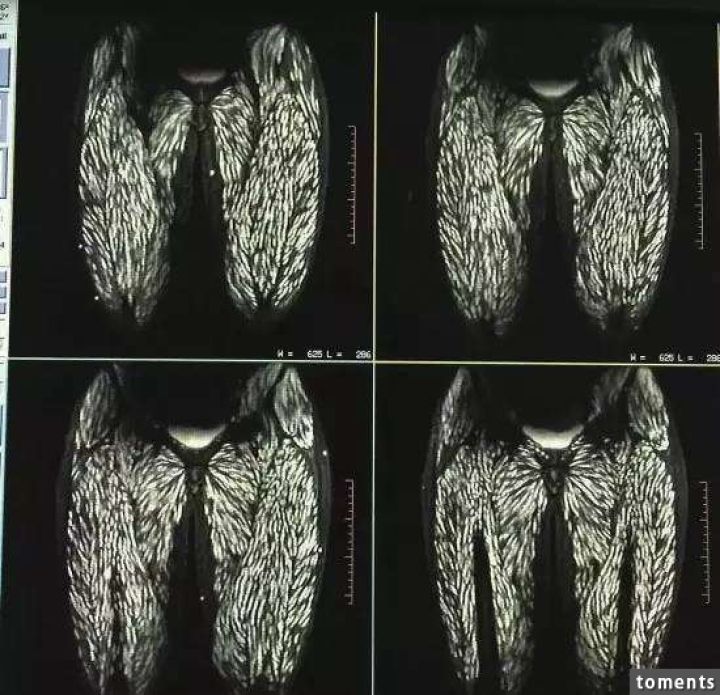

病院では頭部MRIと全身CTスキャンが行われたが、その検査結果は専門家さえも驚く衝撃的なものだった。

それもそのはず、女性の全身はすでに無数の寄生虫に侵されており、大脳や顔面の筋肉にさえも感染が見られるひどい

有様だったからだ。

きれいにサシが入ってんな

画像はジョークだろ?なぁ…?

なにやってんだ馬鹿中国人w

レントゲンなのに骨写ってないな

>>188

MRI